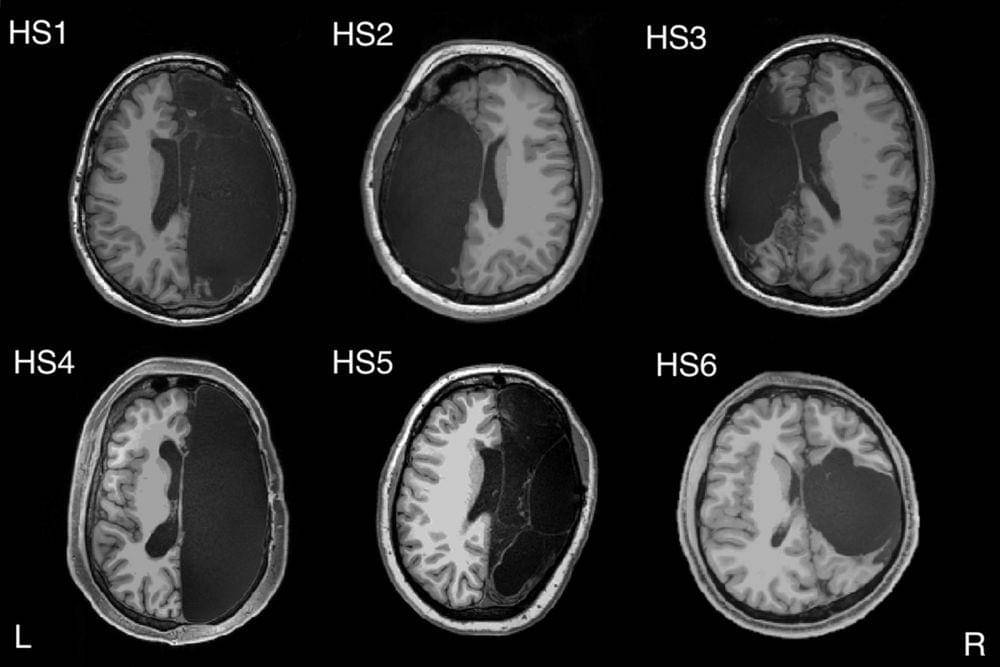

1. Hemispherectomy

Ini adalah praktik kedokteran yang mana setengah otakmu diangkat atau dilumpuhkan. Praktik ini pertama kali dilakukan pada 1923 dan membuat pasiennya lumpuh setengah atau sepenuhnya di sisi tubuh sesuai dengan otak yang dihilangkan.